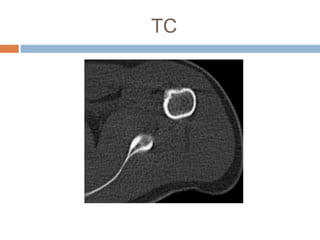

Este documento presenta el caso de un hombre de 37 años con dolor en el hombro izquierdo durante 7 meses. Las imágenes mostraron un nido tumoral en el hombro con características de osteoma osteoide. El osteoma osteoide es un tumor benigno que ocurre comúnmente en varones menores de 30 años y se caracteriza por un nido óseo y esclerosis reactiva. Fue tratado mediante excisión quirúrgica.